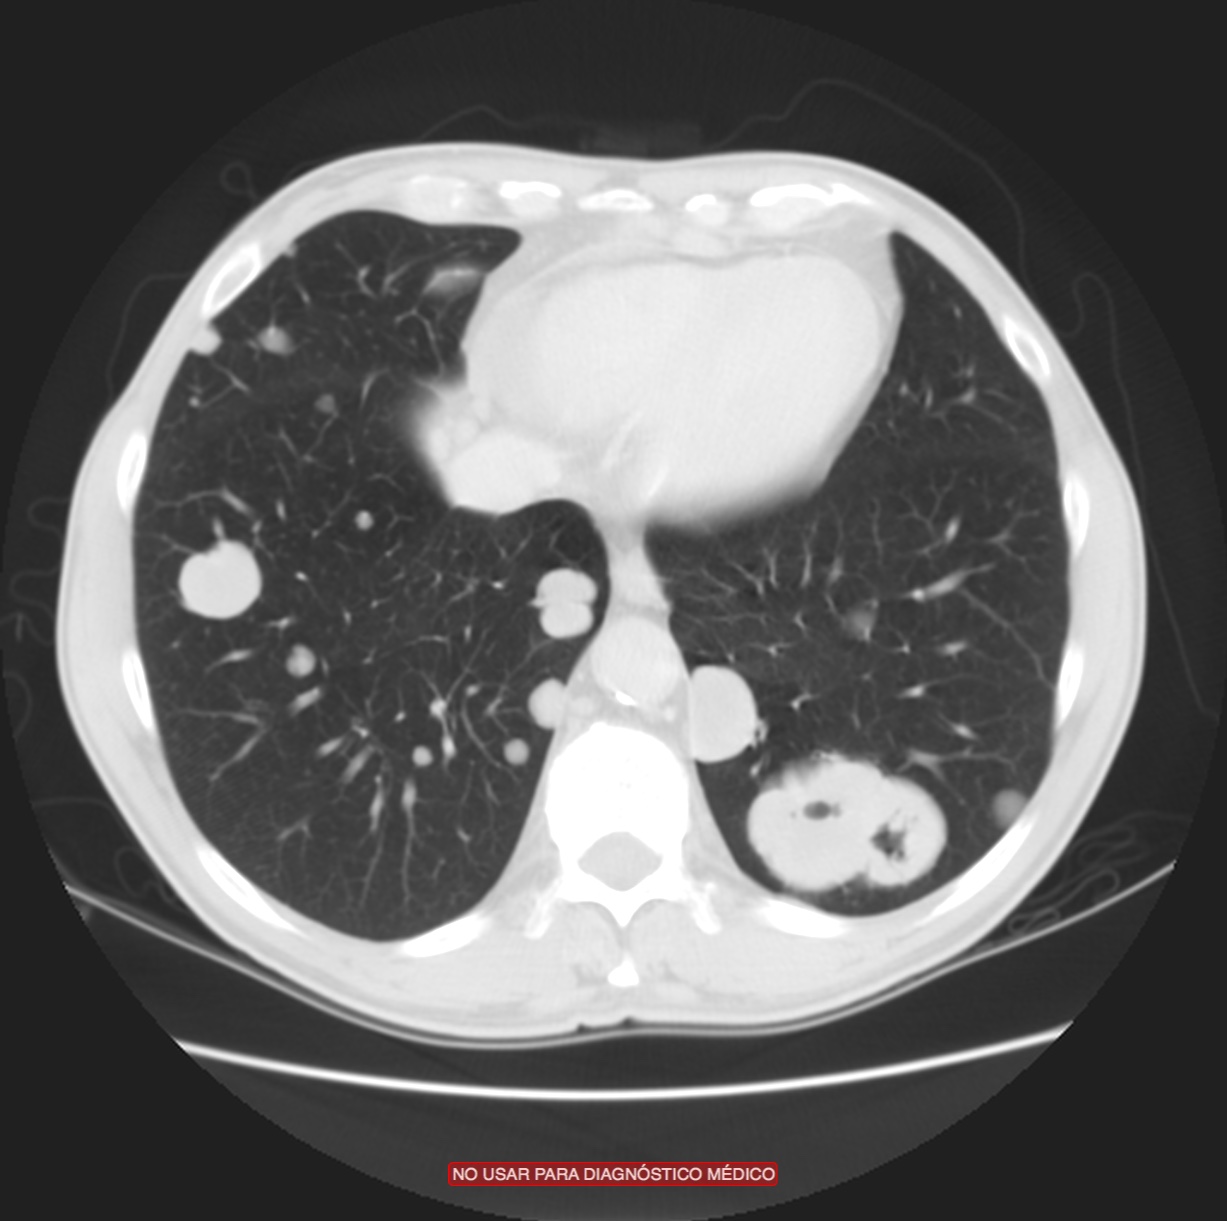

Las metástasis afectan el hígado, pulmones, glándulas adrenales, hueso, bazo, riñones y más raramente el peritoneo. Tumores metacrónicos del tracto superior se dan hasta en el 2-6% de las ocasiones. Una uro-Tc nos sirve para valorar al mismo tiempo la enfermdad metastásica y los tumores metacrónicos del tracto superior en los pacientes de cistectomizados de alto riespo.

Se realiza nueva TC bifásico abdominopélvio y Uro TC.

- Mala evolución radiológica del proceso a expensas de metástasis pulmonares y hepáticas.